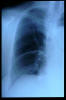

Fractura supracondílea de codo.

Fractura supracondílea de codo.Tras reducción y osteosíntesis.

Fractura supracondílea de codo. Tratamiento con agujas.